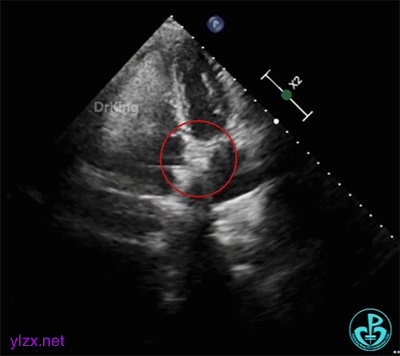

双盘展开后,经胸超声下观察血流,显示无残余分流。

释放封堵器

释放PFO封堵器后,超声下封堵器成型良好,房间隔瘤被夹闭,封堵成功。